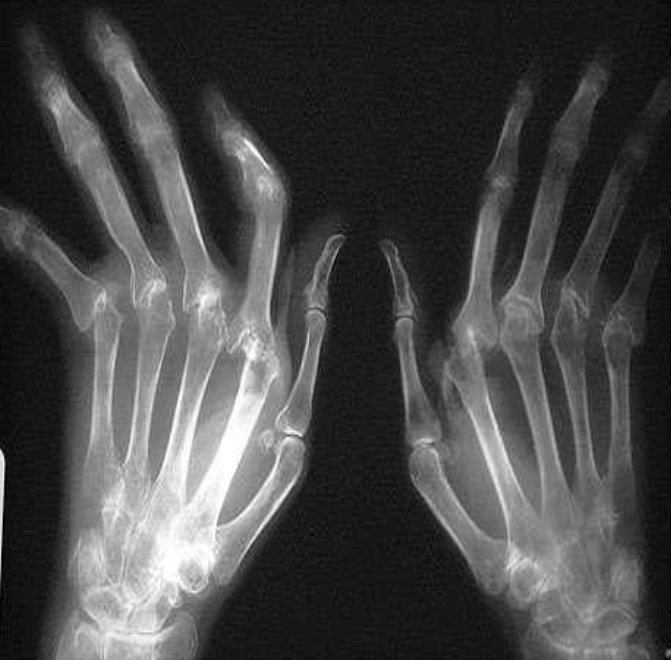

Rheumatoid Arthritis Radiological sign:.

- Around joint, periarticular osteopenia/osteoporosis

- Changes more to the proximal joints than distal

- Swan neck and Boutonnière deformity and extensive erosive